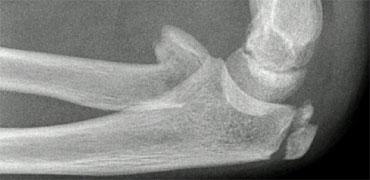

Gãy lồi cầu ngoài (3).

Chẩn đoán gãy lồi cầu ngoài có thể là một thách thức.

Đường gãy đôi khi hầu như không nhìn thấy được (hình).

Ghi nhớ rằng gãy lồi cầu ngoài là loại gãy xương khuỷu tay phổ biến thứ hai ở trẻ em và biết được vị trí cần tìm kiếm sẽ giúp ích cho bạn

Trong gãy lồi cầu ngoài, đường gãy thực sự có thể rất khó nhận thấy vì mảnh xương vùng hành xương có thể rất nhỏ.

Mảnh gãy thường bị xoay.

Tư thế chụp chếch có thể hữu ích, nhưng thường không được thực hiện thường quy (hình).